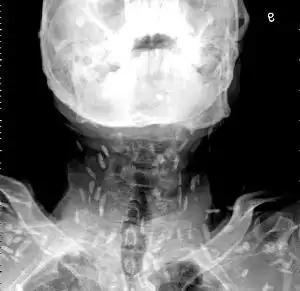

皮肤寄生虫感染|3|11

皮下及肌肉囊尾蚴病